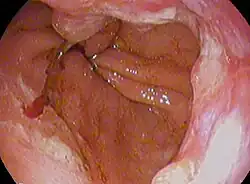

Endoscopic image of an esophageal adenocarcinoma | |

Although an occlusive tumor may be suspected on a barium swallow or barium meal, the diagnosis is best made with an examination using an endoscope. This involves the passing of a flexible tube with a light and camera down the esophagus and examining the wall, and is called an esophagogastroduodenoscopy. Biopsies taken of suspicious lesions are then examined histologically for signs of malignancy.